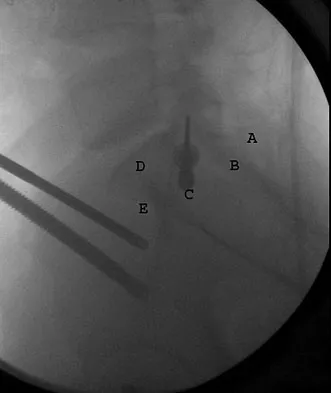

What letter in Figure 33 marks the correct starting point for a transiliac pelvic screw?

Explanation